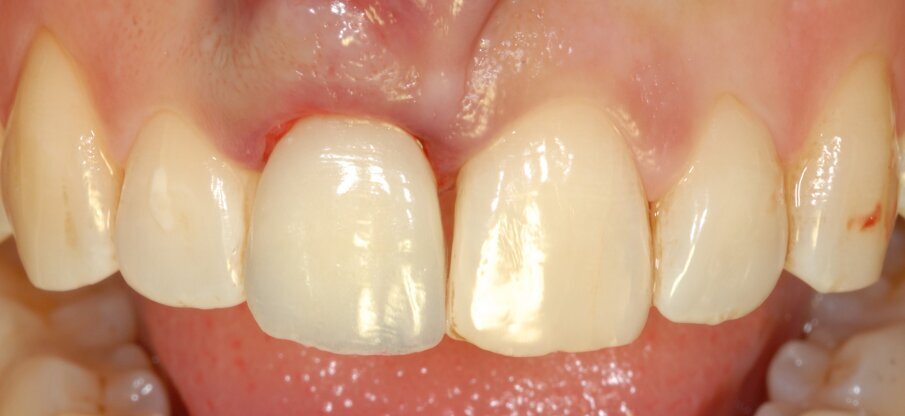

Una paziente di 34 anni di età si è presentata alla nostra osservazione lamentando la mobilità e il colore giallognolo dell’incisivo centrale superiore di destra. Effettivamente, all’esame radiografico era evidente anche un accentuato riassorbimento della radice e si decise così di programmare un impianto post-estrattivo immediato con contestuale inserimento della corona provvisoria e gestione del gap tra le pareti ossee e l’impianto con del biomateriale e dei tessuti molli per mezzo di una membrana a matrice dermica (Figg. 1, 2).

Fig. 1 - L’incisivo centrale di destra appare di colore più scuro e mobile.